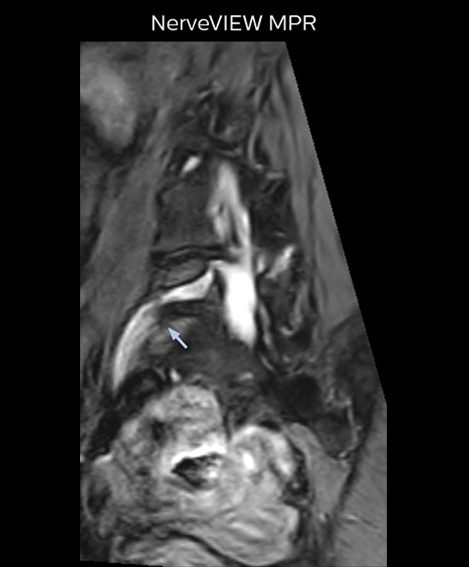

“For example, in sagittal images, when the presence of fat is observed in the intervertebral foramen, it suggests that there is a margin around the nerve. Similarly, the absence of fat indicates that the nerve is being compressed. So, we used to deduce nerve compression indirectly. With NerveVIEW, however, we can observe the condition of the nerves directly, regardless of the presence or absence of fat. We always prefer such direct observation of anatomy over having to make an inference about it.”

“Although symptoms of typical disc herniation and atypical hernia are very similar, the actual site of herniation is different. It is therefore important to characterize the nerve’s condition both inside and outside of the intervertebral foramina. “Conversely, if we see no abnormality in NerveVIEW, we can assume at least that there is no severe condition that requires surgery. Like this, it can help us avoid unnecessary surgery. NerveVIEW can have a tremendous impact in this way.”

“NerveVIEW is really useful for those cases where a nerve disorder is strongly suspected based on the clinical examination but our regular MRI images do not show any findings. These atypical herniations and spinal canal stenosis, occurring in 5% to 15% of the total lumbar herniation/stenosis cases are our main target when using NerveVIEW,” says Dr. Yabuki.